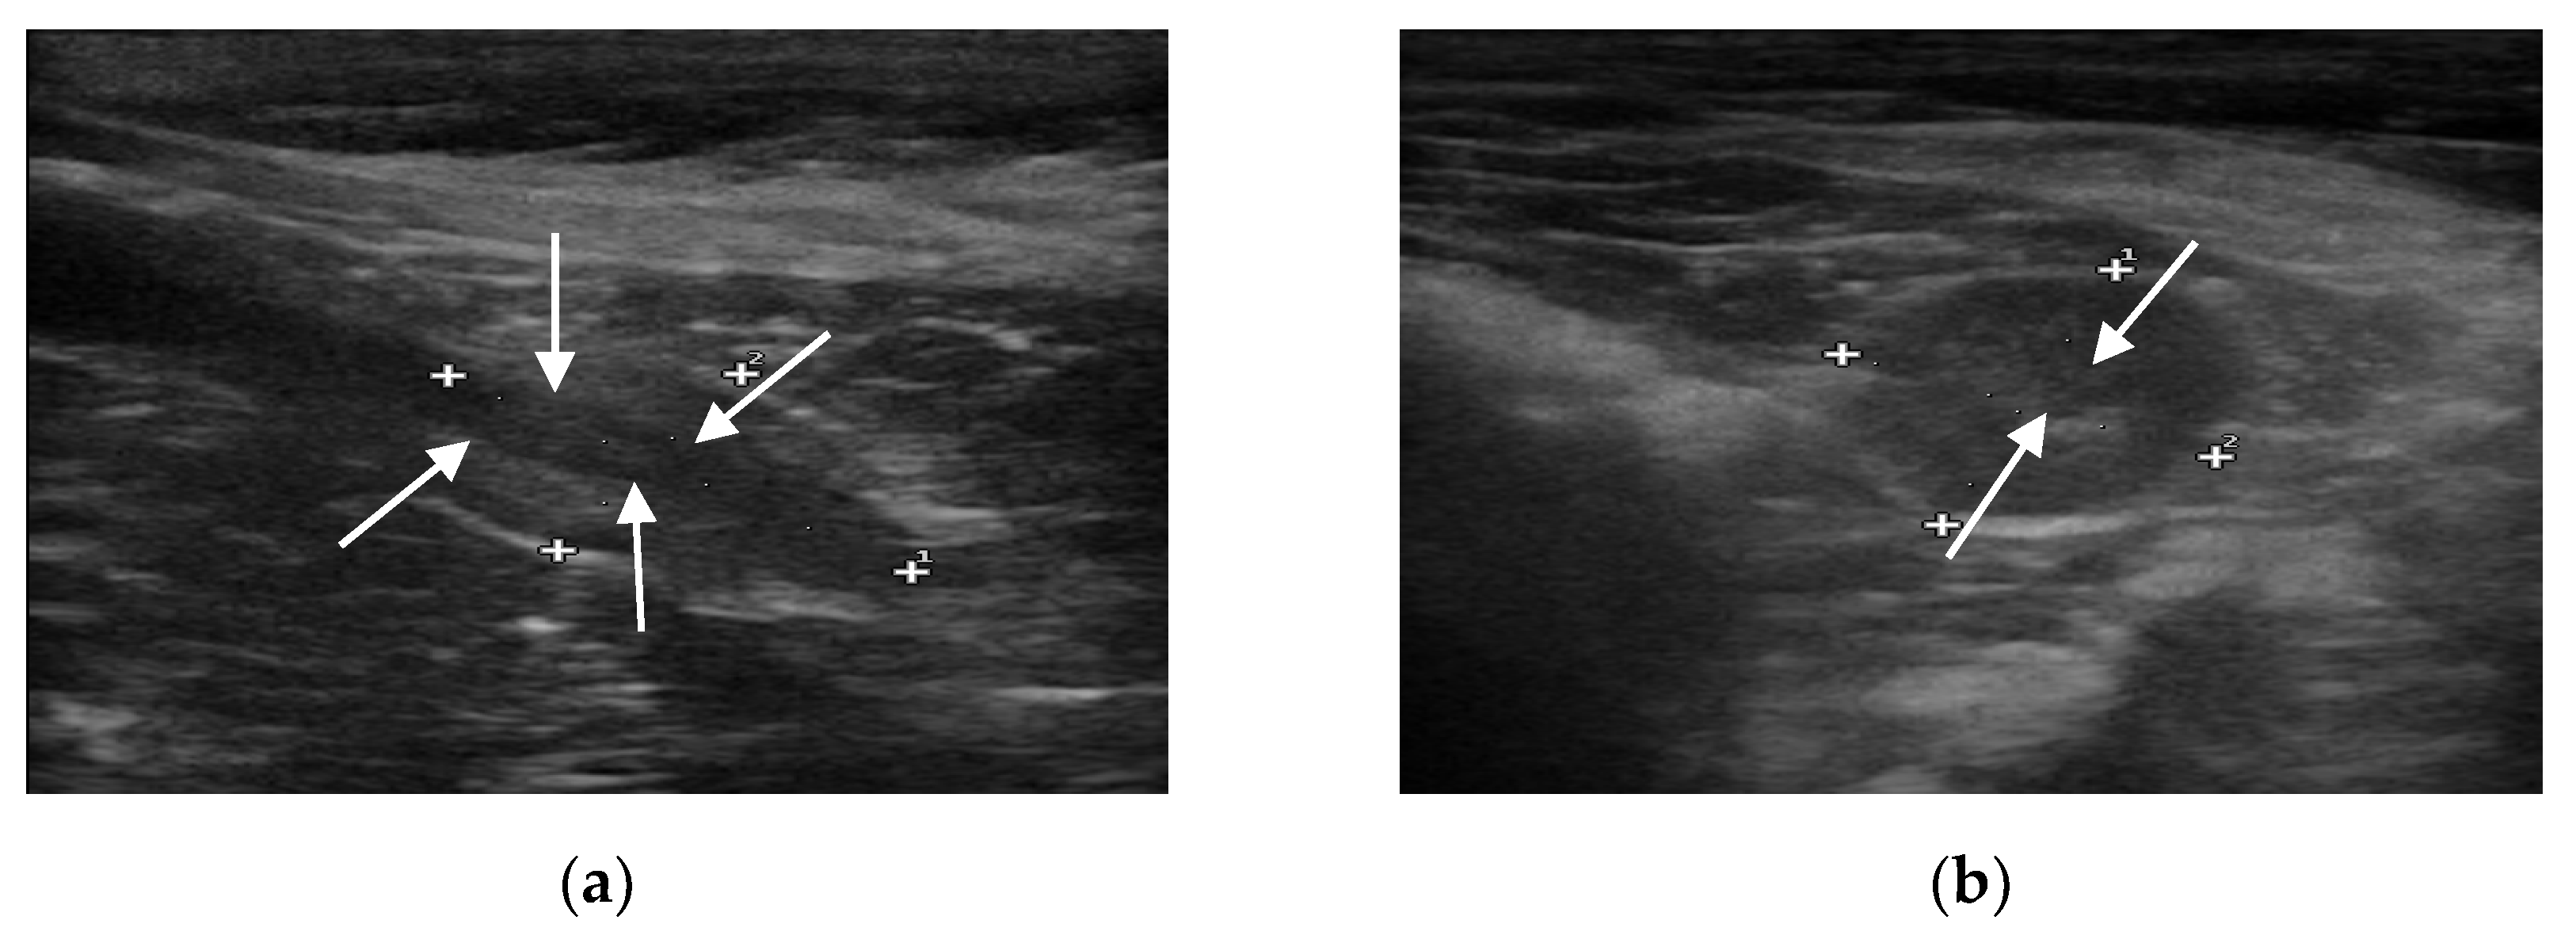

B-mode ultrasound revealed that all the prostate glands had an oval shape with clear and smooth margins, as well as homogeneous and hypoechoic parenchyma. The urethra was always visible as anechoic to hypoechoic linear (in longitudinal view) and rounded (in transverse view) area, surrounded by a hyperechoic wall, which was not always visible (Figure 1).

Figure 1.

B-mode images of the prostate gland (case number 56). (a) Longitudinal view of the prostate gland, which appears oblong in shape, mildly echogenic, compared to the hypoechoic urethra (evidenced with arrows). (b) Transverse view of the same patient, in which the prostate appears ovoidal in shape and, in its center, the hypoechoic circular urethra is visible (evidenced with arrows).